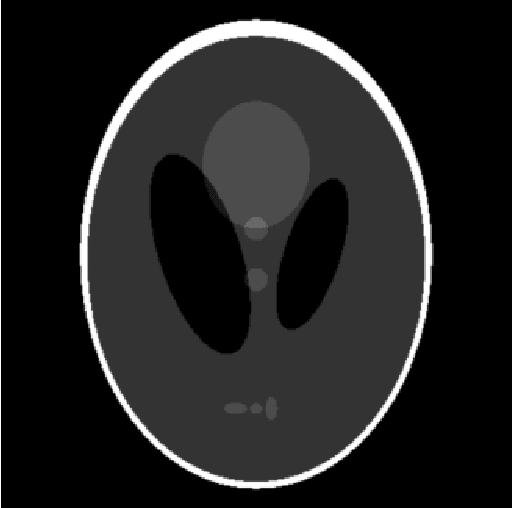

Abstract:We propose an end-to-end differentiable architecture for tomography reconstruction that directly maps a noisy sinogram into a denoised reconstruction. Compared to existing approaches our end-to-end architecture produces more accurate reconstructions while using less parameters and time. We also propose a generative model that, given a noisy sinogram, can sample realistic reconstructions. This generative model can be used as prior inside an iterative process that, by taking into consideration the physical model, can reduce artifacts and errors in the reconstructions.